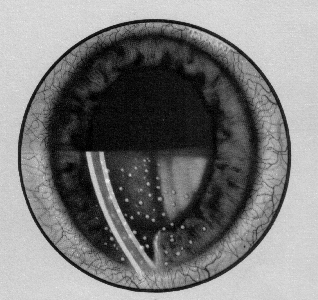

Detectarea tumorilor vezicale prin fluorescenta

Detectarea tumorilor vezicale prin fluorescenta Cistoscopia conventionala si rezectia endoscopica permit vizualizarea si biopsierea anomaliilor mucoase care au expresie macroscopica. Pot exisCiteste tot ... 436 cuvinte

Dimensiune mica

+ cu imagini |